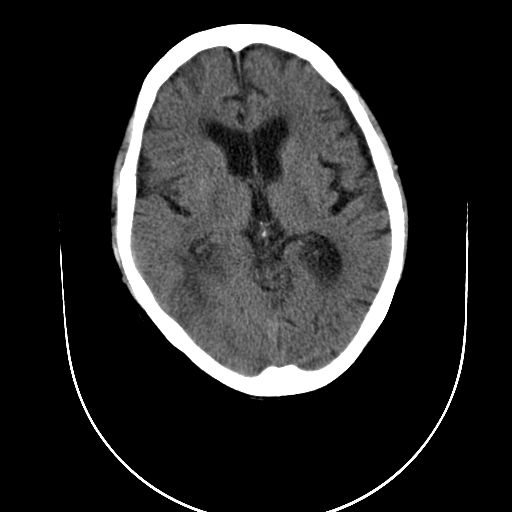

男性  73岁 头昏头痛 乏力。

1)考虑右侧枕顶叶脑转移瘤并肿瘤卒中。2)右侧额叶脑软化灶。

右侧枕顶叶肿瘤卒中,恶性胶质瘤>转移瘤,右侧额叶脑软化灶

平扫见等密度结节并较大范围水肿,内见出血.增强见有明显强化.与大脑镰及颅骨关系不甚密切.脑膜瘤可能性不大.恶性胶质瘤大于转移瘤